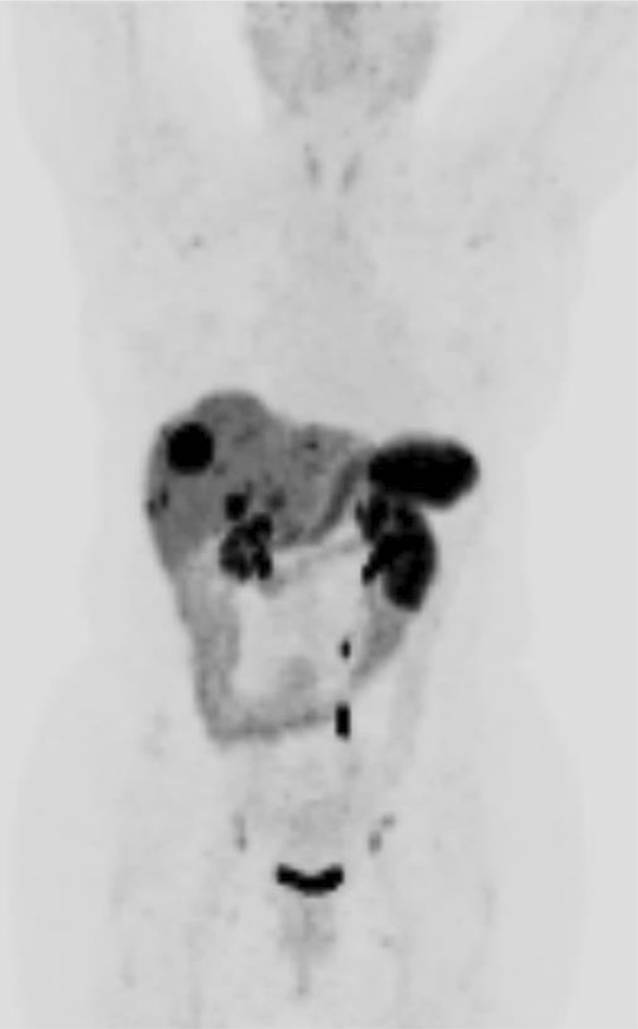

Im Rahmen einer 68 Ga-DOTANOC-PET/CT-Verlaufskontrolle zeigten sich zwei Jahre später neben den bereits bekannten Somatostatinrezeptor-positiven Leberherden in Bezug auf Größe und Anzahl auch erstmalig neu aufgetretene Lymphknoten mit pathologischer Traceraktivität, einerseits im Kopf‑/Halsbereich, andererseits jedoch auch retroklavikulär und axillär sowie inguinal (Abb. 1 und 2).

Abb. 2

68Ga-DOTANOC-PET/CT, Maximum Intensity Projection (MIP): Multiple Leberherde sowie Lymphknoten beidseits inguinal und axillär mit pathologisch vermehrter Somatostatinrezeptor-Expression